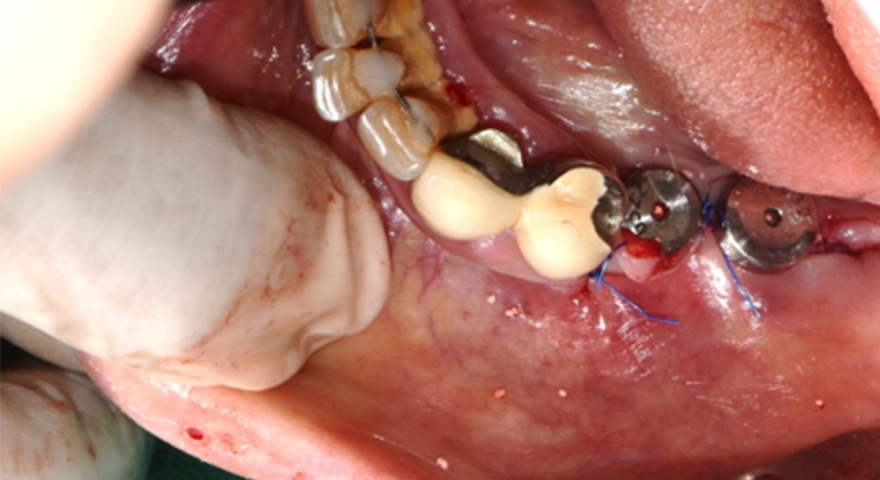

Клінічно спостерігалося повне загоєння без ускладнень. Не було зафіксовано випадків десісценції, інфекцій чи оголення мембран. Всім пацієнтам були встановлені постійні ортопедичні конструкції на імплантатах.

Рис. 2. (A) Пацієнт із виявленою необмеженою (non-contained) втратою кісткової тканини та оголенням імплантату з букального боку на момент встановлення імплантату. (B) Нанесення основного шару пастоподібного кісткового матеріалу перед внесенням гранульованого кісткового трансплантата. (C) Укладання колагенової мембрани з покриттям зони трансплантації — від букального до піднебінного боку — та фіксували за допомогою внутрішніх періостальних швів. (D) Через шість місяців після аугментації — візуалізується регенерація кістки з букального боку в ділянці раніше оголеної різьби імплантату.